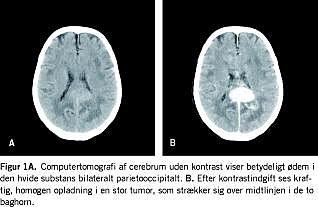

Primære lymfomer i centralnervesystemet (PCNSL) er non-Hodgkin-lymfomer (NHL), som opstår i og er lokaliseret til hjernen, spinalkanalen, subaraknoidalrummet og øjeæblet. Der er tale om sjældne tumorer, som udgør 1-2% af de intrakraniale neoplasmer og 1,5% af alle NHL [1]. I en vestdansk populationsbaseret undersøgelse fra perioden 1983-1994 fandtes en medianalder ved sygdomsdebut på 62 år (spændvidde 15-85 år) ved ikke aids-relaterede PCNSL uden kønsvariation [1]. Der er tale om ekstranodale stadie 1E-lymfomer, som ved sygdomsdebut kan være solitære, multifokale eller diffust leptomeningealt infiltrerende, og som oftest er lokaliseret supratentorielt. Undertiden rejses mistanken om et PCNSL allerede præoperativt ved computertomografi (CT) af cerebrum, hvor man til forskel fra gliomer karakteristisk kan iagttage en homogen kontrastopladende proces (Figur 1 A og B ). Diagnostikken kompliceres ofte, hvis der før operationen kortvarigt er givet behandling med kortikosteroider, idet denne behandling forbigående kan få lymfomvævet til at forsvinde, hvorfor benævnelsen ghost tumour. Den histologiske diagnose stilles i reglen ved stereotaktisk hjernebiopsi, evt. suppleret med cytologisk og flowcytometrisk undersøgelse af cerebrospinalvæske (CSF). Behandlingen vanskeliggøres af blod-hjerne-barrieren, som hæmmer en lang række hydrofile cytostatika i at trænge over i CNS i effektive koncentrationer. Ydermere er den mest effektive behandling, som består af højdosis kemoterapi kombineret med kranial bestråling, behæftet med betydelig CNS-toksicitet, hvor risikoen er størst hos ældre patienter ( > 60 år) og øges med længere overlevelse [2]. I det følgende gives der på baggrund af en litteraturgennemgang en oversigt over nyere behandlingsmuligheder af PCNSL, hvor også antistofbehandling og radioimmunterapi vil blive omtalt.